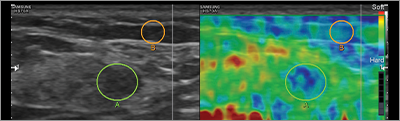

• 의료진의 진찰과 검사(초음파 등)를 통해 결정됩니다.

가슴구조 1mm 단위 분석!

- 유선·지방·근막·피부 세부 구조 분석

[ 해부학적 구조진단 ]

유선-지방-근막-피부탄성-혈관까지

가슴구조 360도 다층 분석!